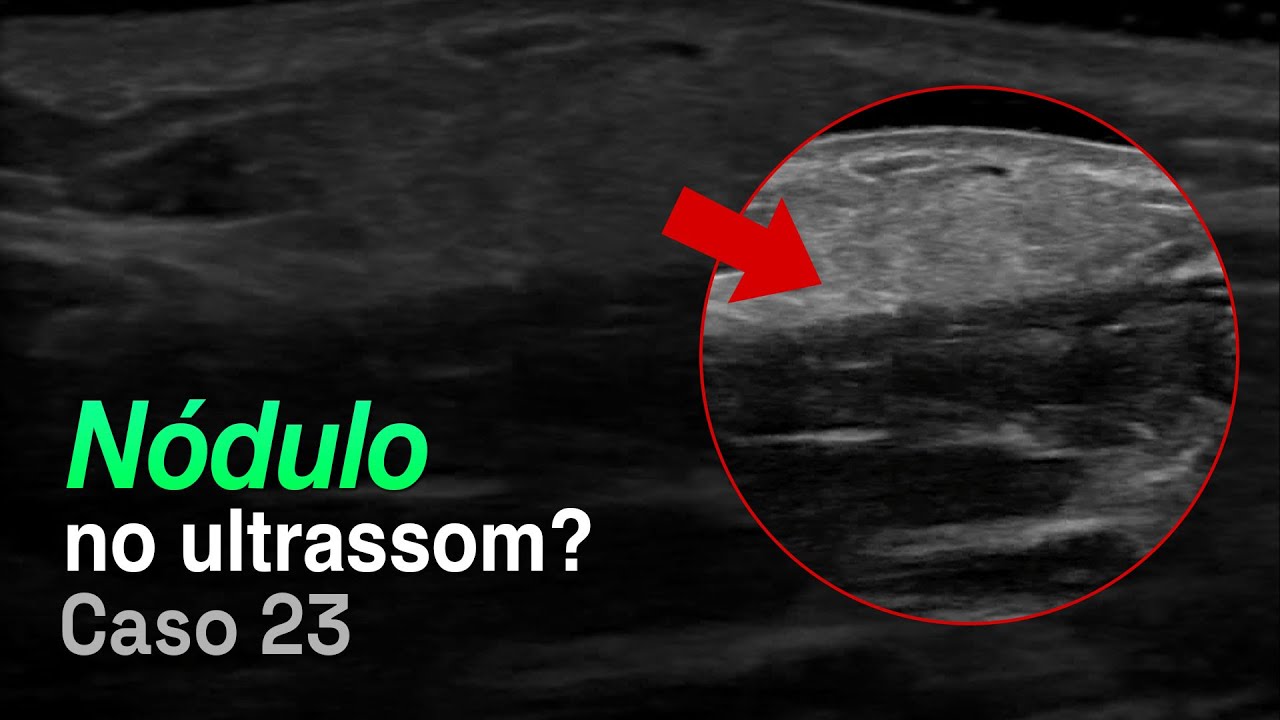

ultrassom que é a ferramenta de escolha para avaliar a tireóide qual que é a expectativa a expectativa é que as características da doença benigna da doença maligna sejam completamente diferentes mas qual é a realidade que a gente encontra a zona de intercessão dessas características muitas vezes é extensa algumas características estão presentes em doenças benignas e malignas isso dificulta para a gente a responder uma pergunta muito importante quais são os novos que precisam de atenção e identificou o módulo de tireóide e aí que eu faço com esse nome de tireóide o objetivo do das classificações que

se vai acompanhar por um período curto de tempo reavaliar e e tomar a sua decisão é em um outro momento então às vezes isso é ponto de atrito é a gente é muito perguntado de como é que a gente faz na prática tem é tão o eu descrevo modo clássico o nódulo e encaminha para o proinfa beleza mas será que a gente consegue aplicar isso na prática bora lá esse é o módulo governo na composição do novo álbum no sólido dois pontos é que o gene cidade do lado lembra que é comparativa com para um

parente mágoa ou muito e aí como você faz compara com um músculo mais preto que o músico três pontos a morfologia mas lá a globo ou mais alto mais alto também ah mas eu não sei está no longitudinal está no transverso olha carótida em nota à tireóide você vai ver que é um corte axial e aí ele é mais alto do que lamentam ganha três pontos margens as margens são elas são todos os lados lei regulares dois pontos foto sacou genéricos se você olhar com muita cautela você vai ver uns pontinhos a kolynos no interior

três pontos então você classifica assinando como tierra de 5 alto risco de malignidade provavelmente colega vai optar por uma função e vai confirmar uma base aqui consegue entender estudo se não consegue volta a dividir lembra dos pilares vamos resumir de hades cinco pilares composição é cogente cidade margem forma é mais alto do que ela e os focos a cogeco beleza 5 quanto maior pontuação maior o risco de malignidade isso ajuda a definir a conduta se você gostou da um jovem no vídeo deixe sua sugestão quente ainda está tentando alguns modelos para encontrar um modelo mais